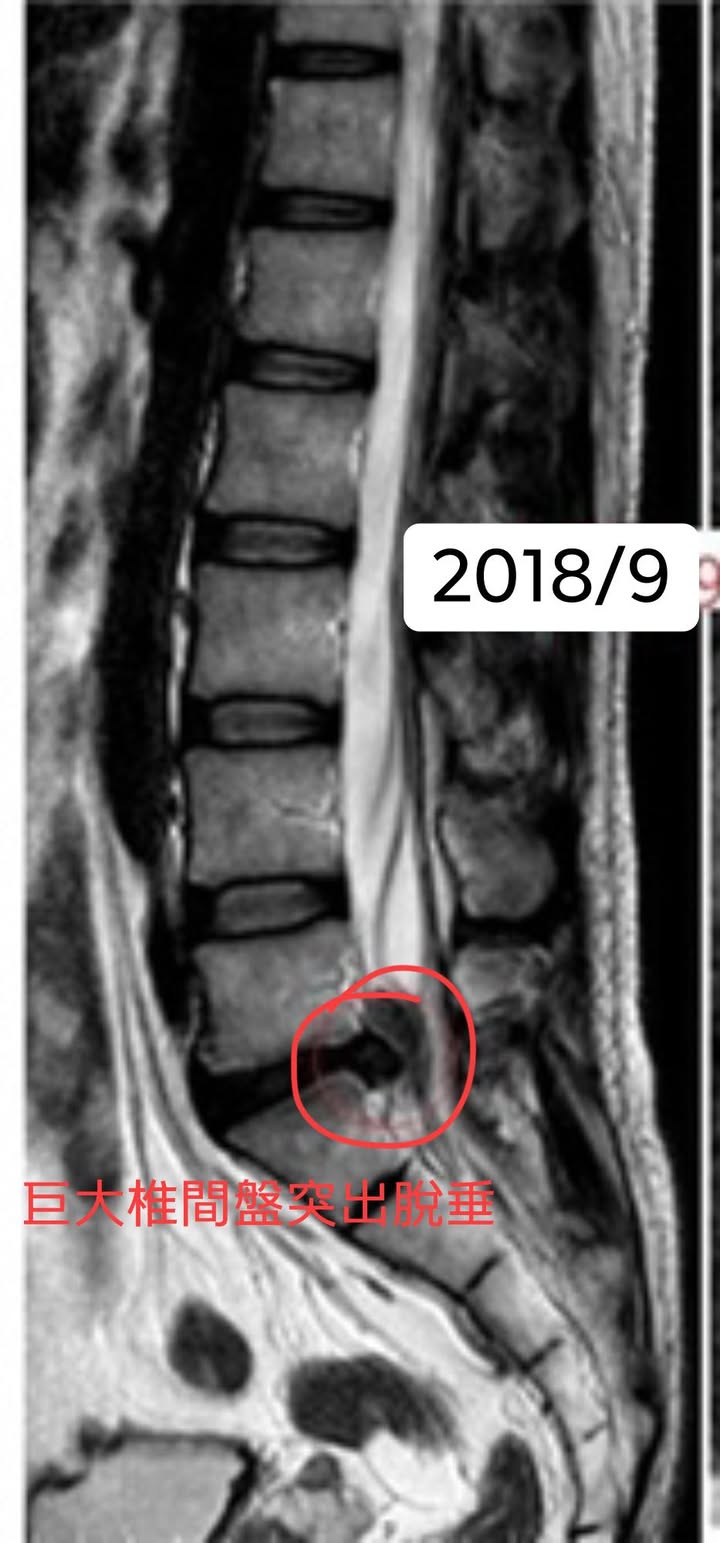

Cervical Spine Treatment Cases 腰椎治療案例 #腰椎手術失敗綜合症候群 #術後沒保養還是又繼續椎間盤突出 #感謝台北梁小姐熱情見證 ... 2021.03.02 #超感動醫案感謝中壢姚阿姨見證 #原本已經坐輪椅的人生看到一絲希望 #脊刻救援牛轉乾... 2021.02.22 #感謝新北中和區陳大哥熱情見證 #從北到南看過眾多中西醫民俗療法 #腰痛到連躺跟坐都... 2021.02.17 #感謝桃園龜山蘆先生熱情見證 #腰椎跟屁股痠痛超過十二年 #腰椎纖維環裂隙導致神經根... 2021.02.16 #騎馬摔傷腰椎醫案 #感謝內湖陳先生熱情見證 #椎間盤突出合併輕微椎間孔狹窄 #重新騎... 2021.02.03 #巨大椎間盤突出醫案 #脊椎整合中醫微創逆轉勝 #感謝三峽林先生熱情見證 #為何突出的... 2021.01.29 #腰椎粉碎性骨折手術後調養醫案 #坐輪椅的人生終於看到希望 #脊椎手術失敗症候群 #Fai... 2021.01.26 #感謝台中市大肚區患者熱情見證 #第二次治療腰痛好超多 #腰酸痛時間快一年了 #親筆寫... 2020.12.05 #腰椎嚴重滑脫醫案 #原本左腳麻痛無法久站超過十分鐘 #脊椎整合中醫微創療法逆轉勝 #... 2020.12.02 #感謝林口楊先生熱情見證 #椎間盤整和中西醫微創療法逆轉勝 #曾經大痛到無法走路嚴重... 2020.11.25 #今天來聊巨大骨刺為何可以吸收回去! #椎間盤突出需要多久才能吸收呢? #馬尾神經症候... 2020.11.10 #腰椎滑脫一定要開刀嗎? #骨科認為開刀置放骨釘穩定錐體 #如果患者可以藉由增強肌... 2020.11.04 #六年的長期腰酸痛醫案 #原來是椎管狹窄合併輕微突出 #每年冬天準時發作苦不堪言 #感... 2020.10.31 #椎管狹窄案例 #感謝新莊陳大哥熱情見證 #腰酸痛數年原來是椎管狹窄 #來診前已經痛到... 2020.10.28 #知名四代魚丸店掌門人熱情見證 #腰椎中醫微創逆轉勝 #椎間盤突出醫案 #感謝新北... 2020.10.23 ← 上一頁 8 9 10 11 12 下一頁 →